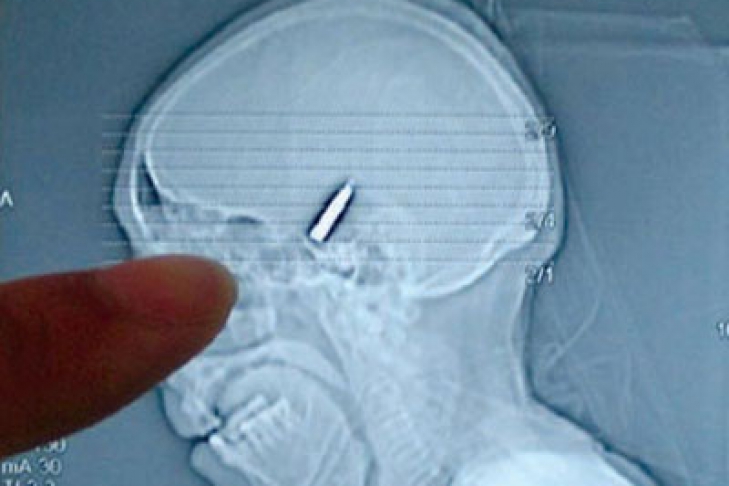

До чего же удивил врачей 28-летний итальянец Дарко Санджермано. Он чихнул пулей, которую те как раз готовились вытянуть.

Пулю в голову парень получил случайно. Житель Турина приехал со своей девушкой на рождественские праздники в Неаполь. Прогуливаясь по городу, он внезапно получил пулю в висок. Кто выпустил снаряд 22-го калибра, неизвестно, но, вероятнее всего, пуля срикошетила в Дарко. У итальянца началось сильное кровотечение, и его отвезли в больницу.

Но пока врачи готовились к срочной операции по извлечению из черепа пострадавшего инородного тела, Санджермано чихнул. В этот момент пуля вышла через правую ноздрю. Невзирая на то, что серьёзных травм итальянец не получил, его височная кость была повреждена, а осколки попали в глаз. В связи с этим его всё-таки решили прооперировать. Еще одну операцию пациент должен перенести в родном Турине. Врачи говорят, что жизнь и зрение итальянцу спасло то, что пулю очень затормозило столкновение с черепом.